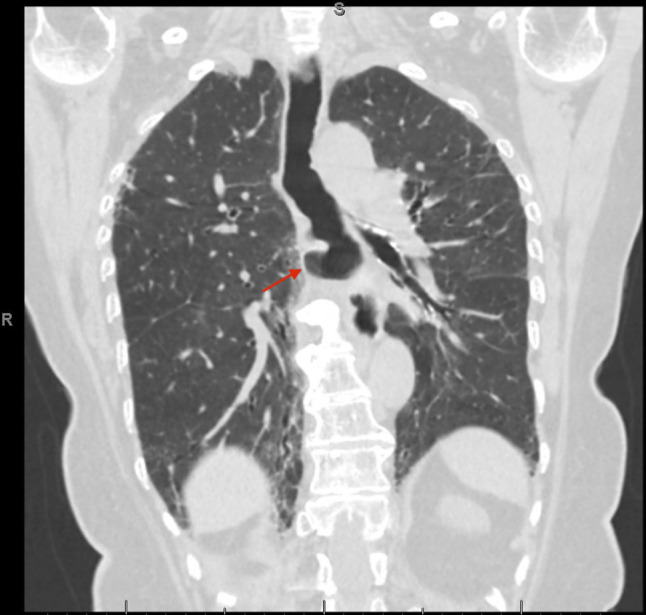

经食管超声心动图通常用于指导结构性心脏干预,但有食管损伤的风险。我们报告一位79岁的女性,她接受了经导管二尖瓣边缘修复术,并发食道血肿。急性胆囊炎并发难治性消化道出血及败血症。尽管采取了积极的措施,她还是没能活下来。我们的病例显示了经食管超声心动图相关并发症的潜在严重性,特别是在有食道憩室和抗凝使用等易感因素的患者中。

Transesophageal echocardiography is commonly used to guide structural cardiac interventions but carries a risk of esophageal injury. We present a 79-year-old woman who underwent a Transcatheter Edge-to-Edge Repair of the mitral valve and developed an esophageal hematoma. Clinical course was complicated by intractable gastrointestinal bleeding and sepsis due to acute cholecystitis. She did not survive despite aggressive measures. Our case demonstrates the potential severity of transesophageal echocardiography-related complications, especially in patients with predisposing factors such as esophageal diverticula and anticoagulation use.